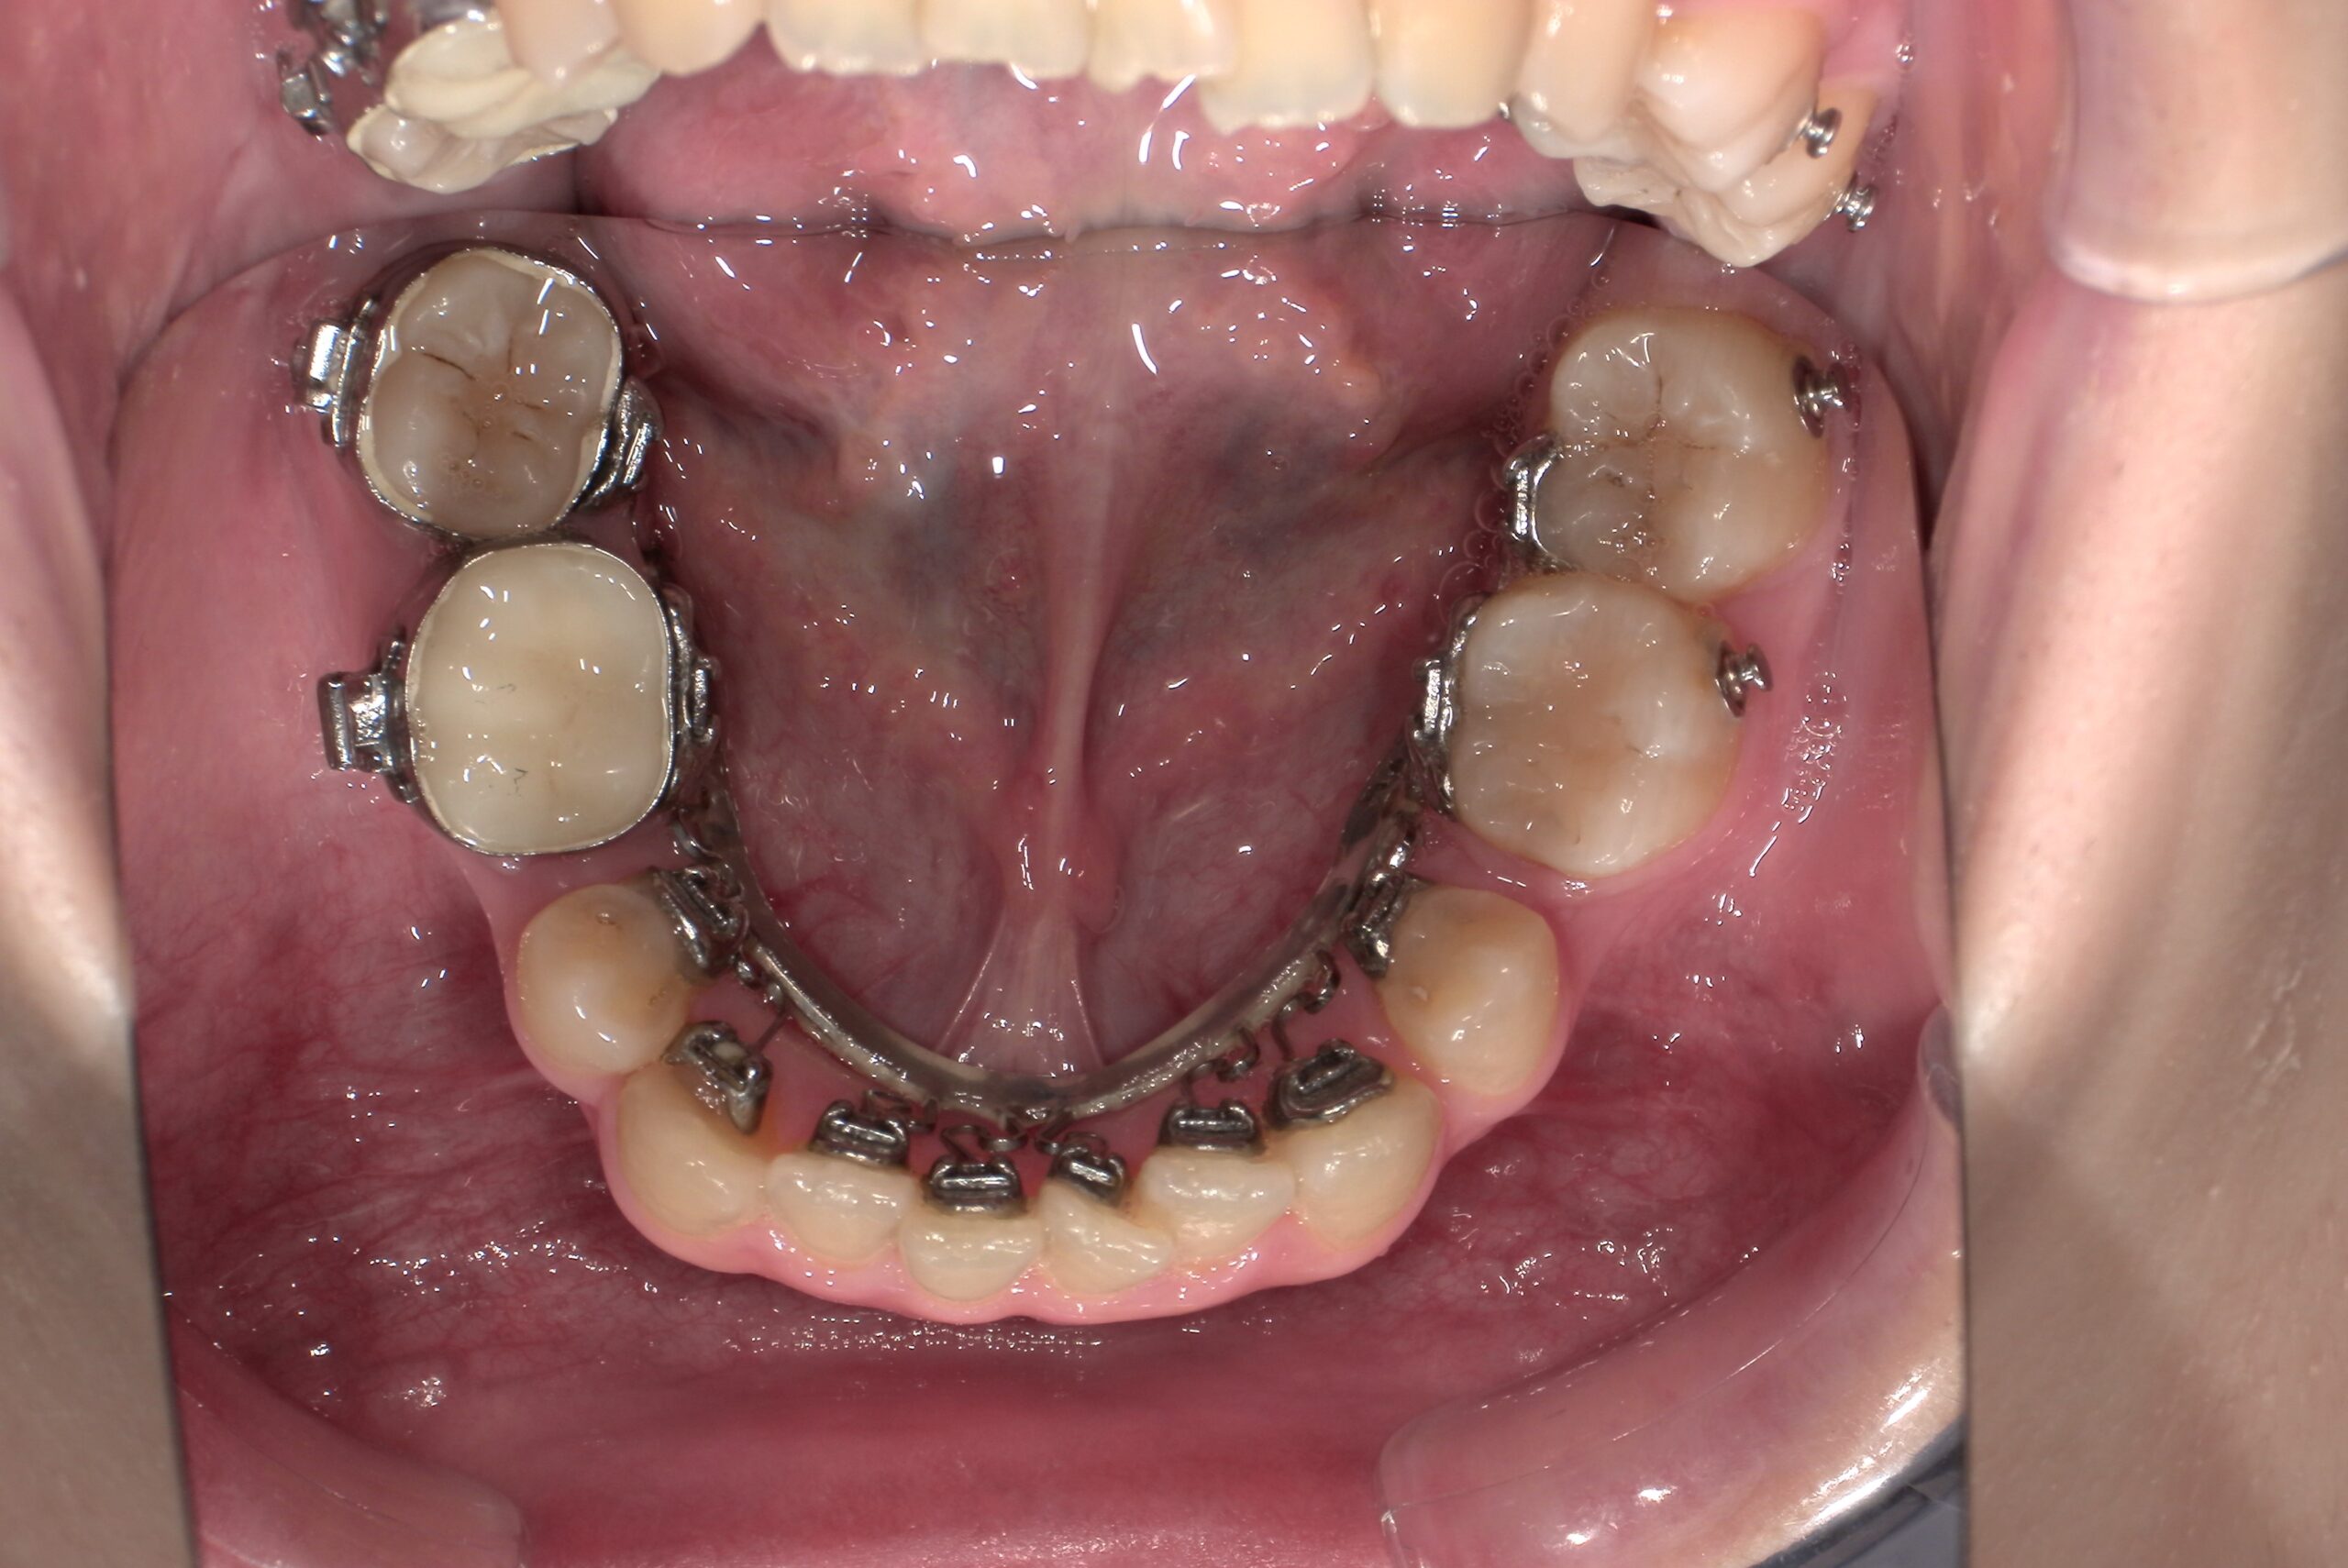

📸治療経過写真

当院で裏側矯正治療しているスタッフの経過写真をご参考にしてください。

上下左右小臼歯を1本ずつ計4本抜歯して現在も治療中です。「歯を抜いた隙間が閉じた量」、「前歯の移動量」、「正面から見た前歯の位置」に注目して見てもらえると、歯の移動の早さが目に見えて分かるかと思います。

初回装着時

下顎